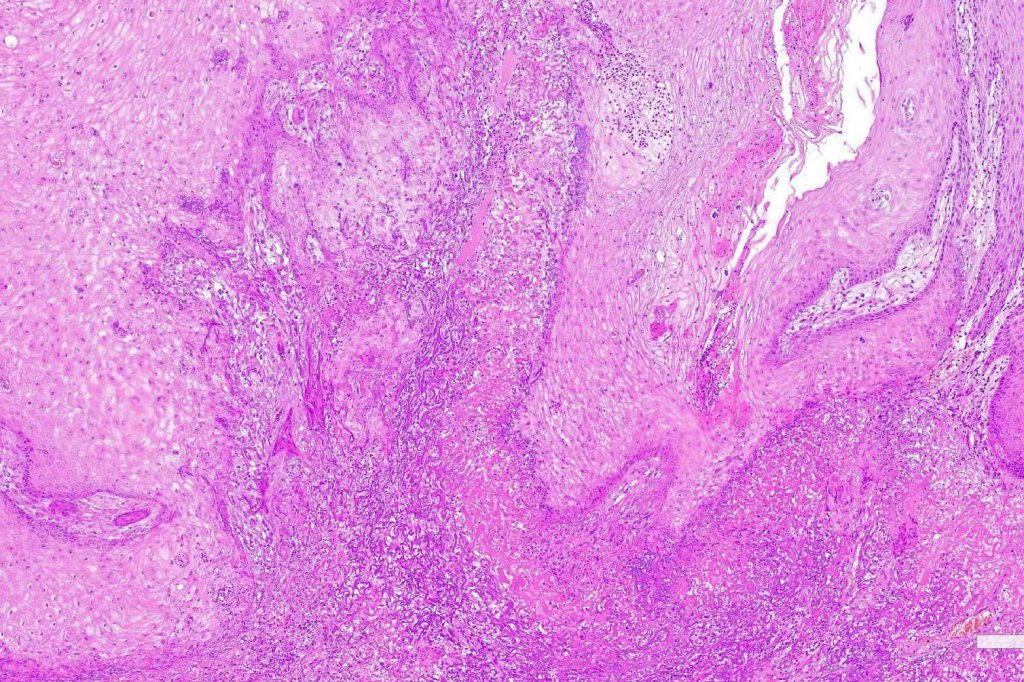

•With evolution, the epithelium flattens with underlying fibrosis and chronic inflammation including a foreign body giant cell reaction to keratin

. Exceptionally, perineural infiltration and vascular involvement has been documented. If present, this should be viewed with concern as risk of recurrence or metastatic spread is significant

Below is a fascinating case shared on McKee Derm by Dr. James Simpson. There is an obvious keratoacanthoma but at the edge of the lesion there is marked atypia with nuclear enlargement and pleomorphism. This is also evident in the adjacent epidermis and in the deeper nests.